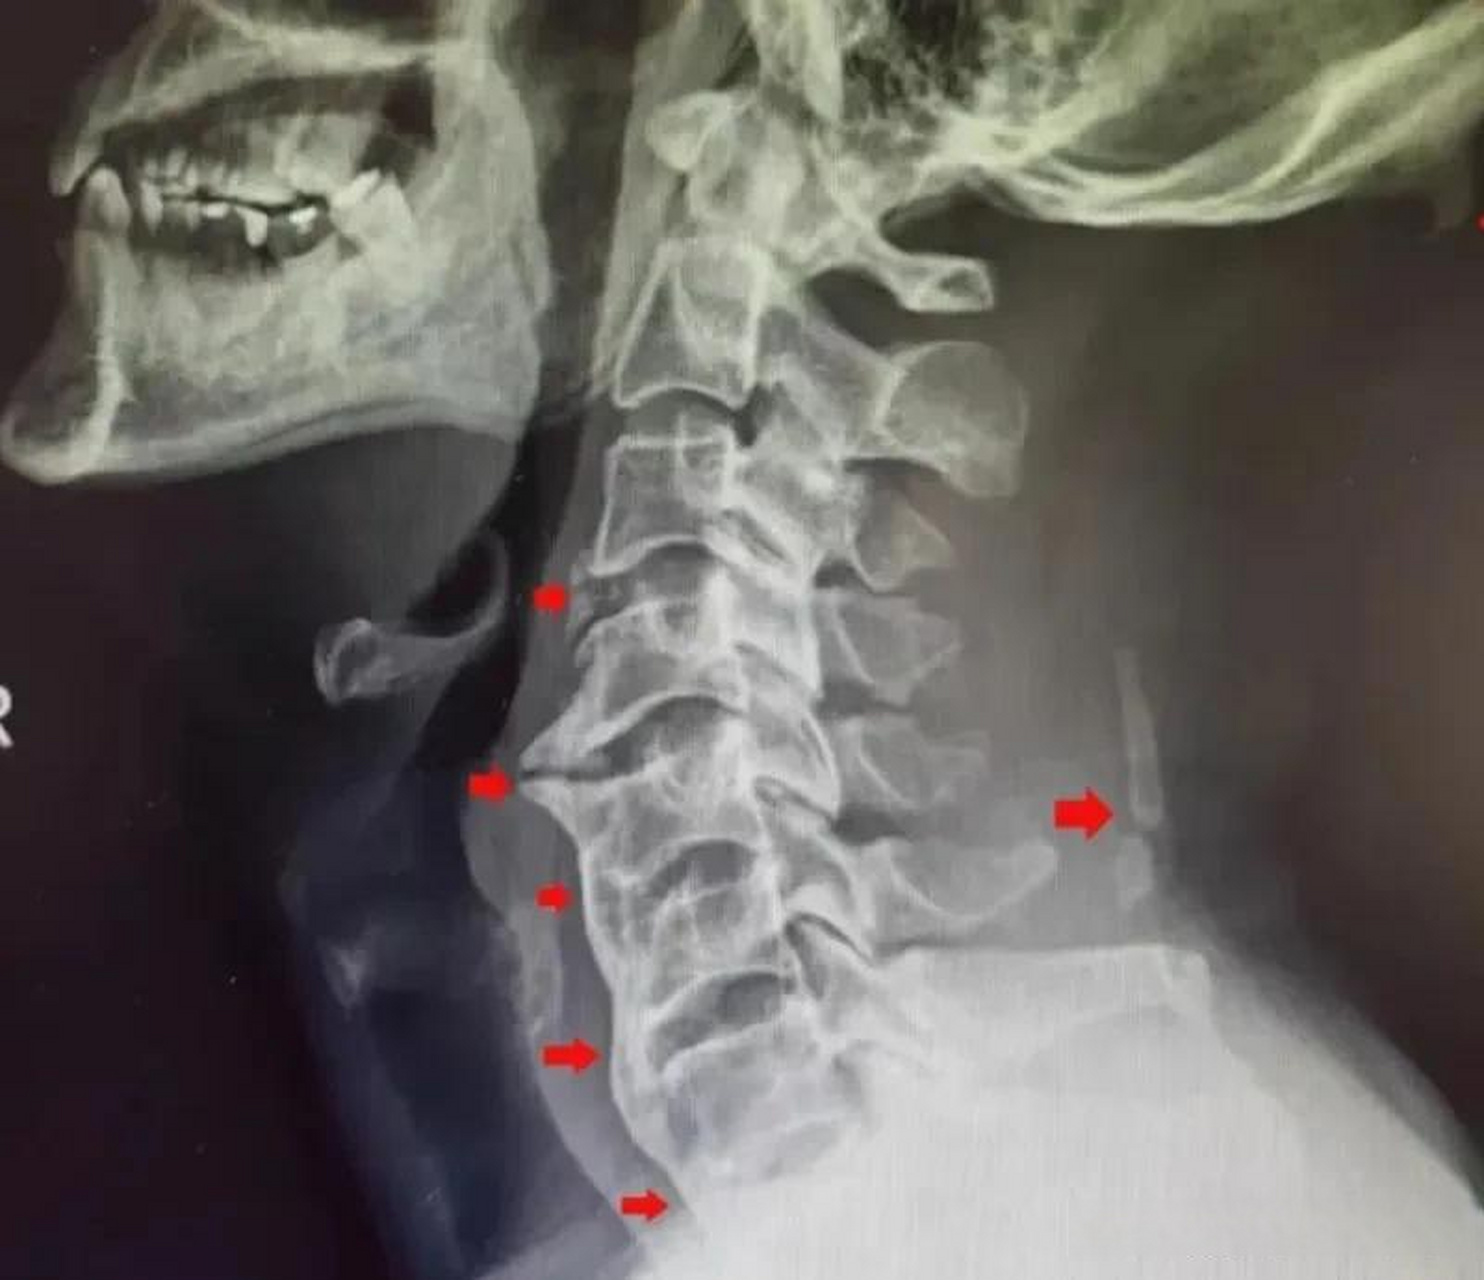

椎侧位x线片颈椎生理前凸曲度尚可,从c34椎间隙开始向下,所有的前纵

颈椎x线片显示c4-5至c7-t1之间的胸椎侧弯伴颈椎病.

x光片-颈椎,红色表示疼痛部位